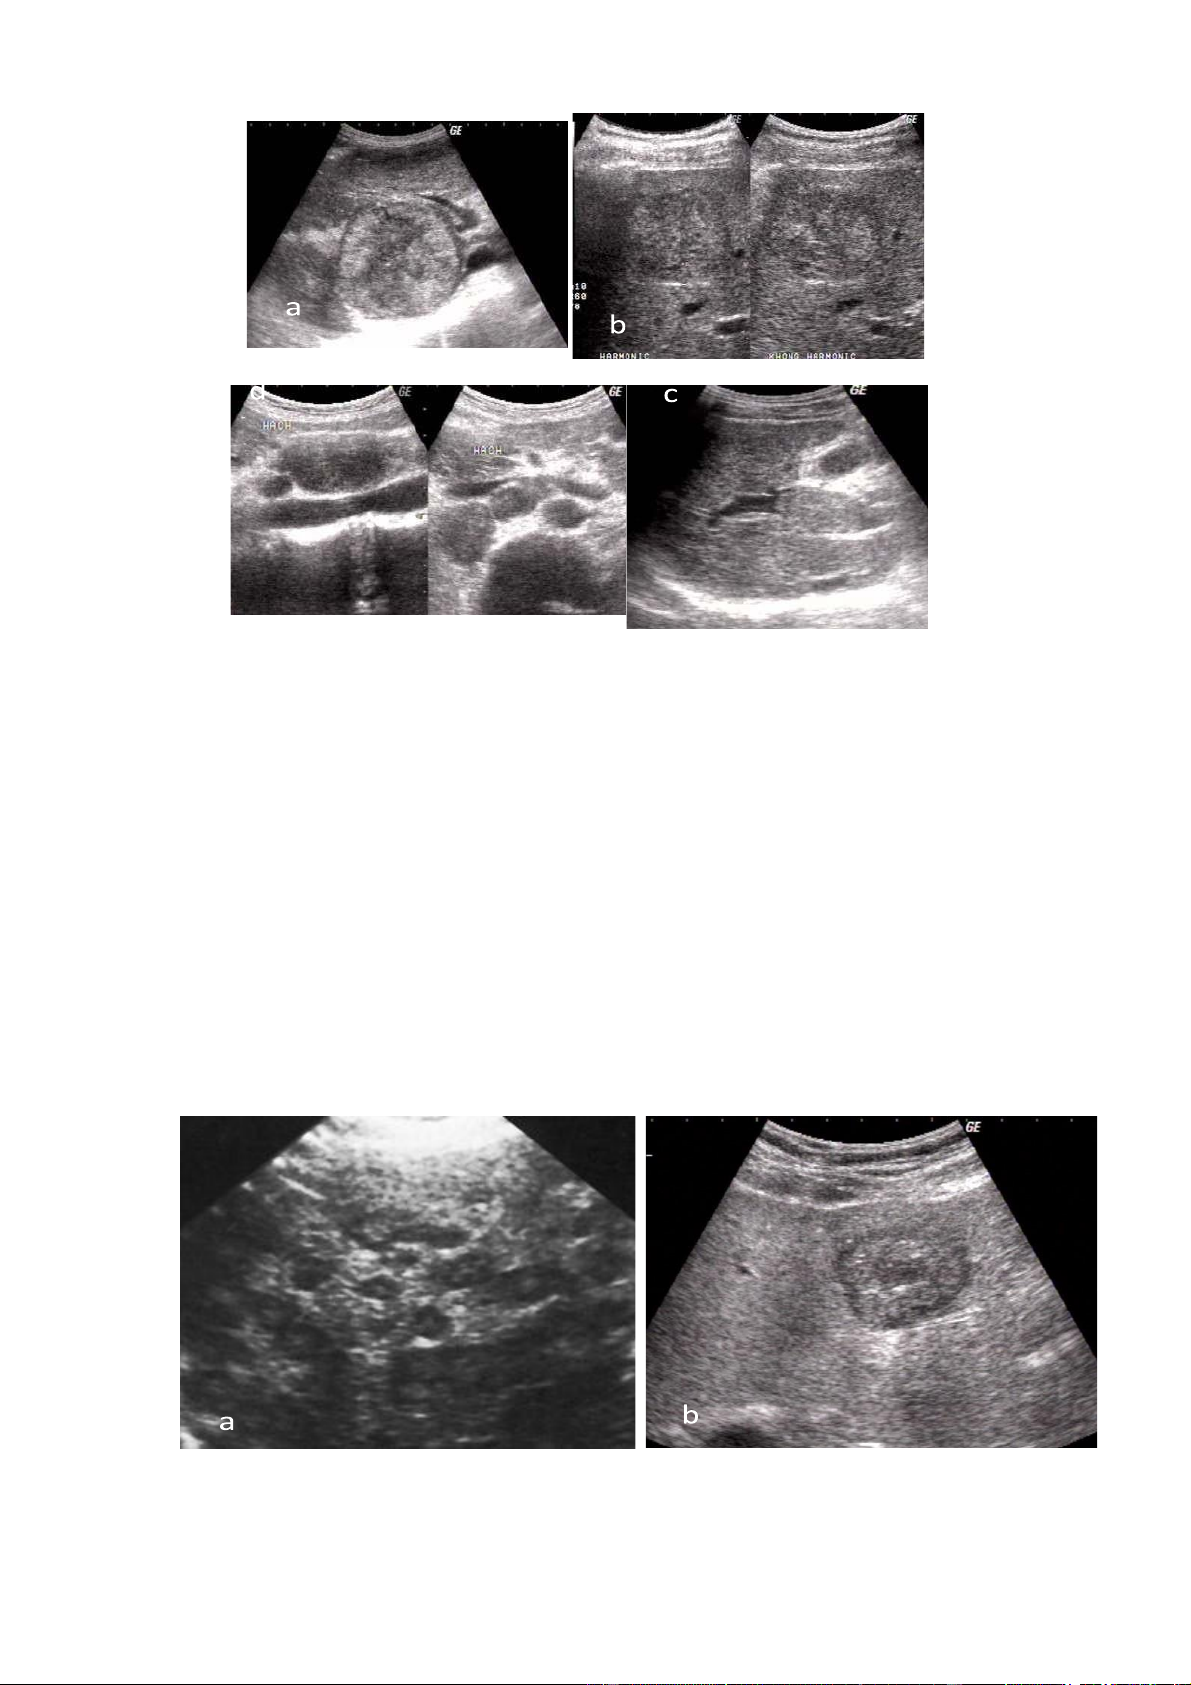

Hình 4.1 . U tế bào gan ác tính

a. Khối u tăng âm với viềm giảm âm xung quanh và hoại tử trung tâm

b. Khối u đồng âm với viền giảm âm xung quanh khối

c. Huyết khối tĩnh mạch cửa d. Di căn hạch 4.3. Di căn gan

Hình 4.3.1. Ung thư đại tràng di căn gan lOMoAR cPSD| 58490434

a. Di căn thể nhiều nốt nhỏ rải rác trong nhu mô với các hình tăng âm nhẹ

và viền giảm tỷ trọng bao quanh; b. Di căn thể một khối lớn tăng âm nhẹ,

vôi hoá nhỏ và viền giảm âm rõ.

Hình 4.3.2.. a. Di căn của ung thư biểu mô vòm họng

b. Di căn của ung thư buồng trứng; c. Di căn của ung thư hạch